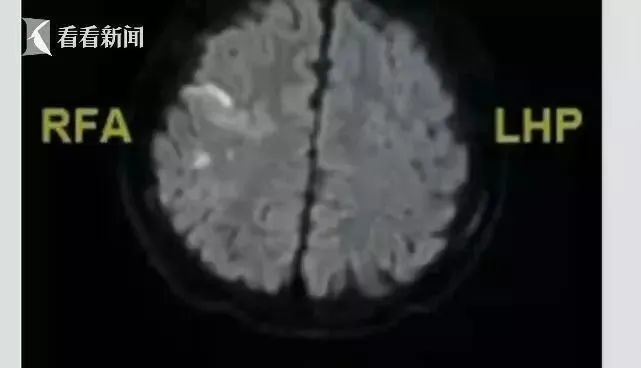

经过检查 , 医生诊断小男孩得了脑梗塞

南大二附院急诊科主任医师熊申生:

“溶栓大概一个小时以后 ,

他左上肢肌力基本恢复到正常水平 ,

他就能动了 , 肌力稍微差一点 ,

比正常人稍微差一点 。 ”